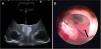

We describe the case of a 3-month-old boy who was admitted to our centre with signs of raised intracranial pressure. Neuroimaging studies showed a third ventricular mass with associated hydrocephalus. The patient underwent complete tumour removal through a transfrontal approach and ventriculo-peritoneal shunt surgery. Postoperative course of the child was uneventful and follow-up magnetic resonance imaging revealed no residual tumour. Histopathology of the resected lesion confirmed the diagnosis of choroid plexus papilloma.